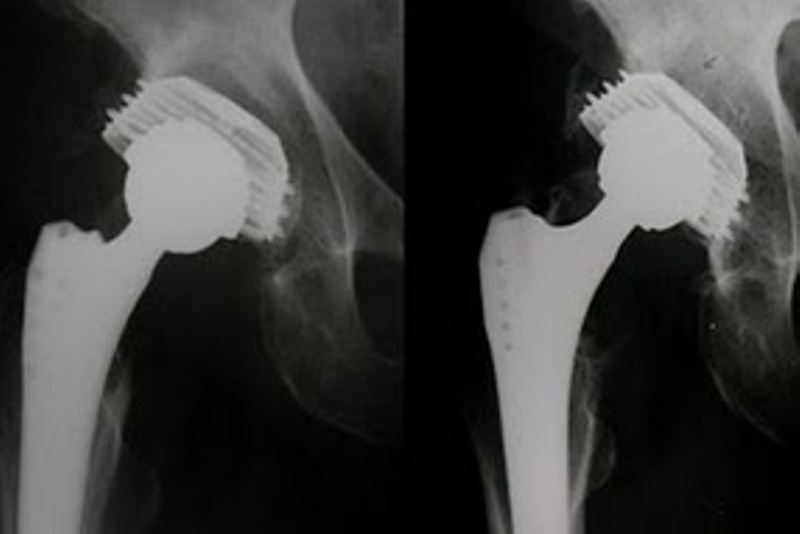

Η διάγνωση γίνεται ακτινολογικά. Αν η περίπτωση του κατάγματος είναι πολύπλοκη η διάγνωση γίνεται με αξονική τομογραφία τριών διαστάσεων και με μαγνητική τομογραφία.

Σκοπός της θεραπείας είναι η ανατομική ανάταξη. Κατάγματα των δυο κολώνων χωρίς μεγάλη παρεκτόπιση καθώς και χαμηλά εγκάρσια κατάγματα μπορούν να αντιμετωπιστούν συντηρητικά με σκελετική έλξη. Κατάγματα με μεγάλη συντριπτικότητα  των οποίων δεν γίνεται ανάταξη η θεραπεία είναι συντηρητική με σκελετική έλξη.

Σε όλα τα κατάγματα της κοτύλης με παρεκτόπιση πρέπει να γίνεται κλειστή ανάταξη με γενική αναισθησία. Αν η ανάταξη είναι ικανοποιητική γίνεται σκελετική έλξη για 8-12 εβδομάδες, αν δεν είναι γίνεται χειρουργική ανάταξη και σταθεροποίηση. Η χειρουργική θεραπεία καλό είναι να γίνεται 3-5 ημέρες μετά το κάταγμα και όχι περισσότερο από 10 ημέρες όπου η ανάταξη γίνεται με δυσκολία.